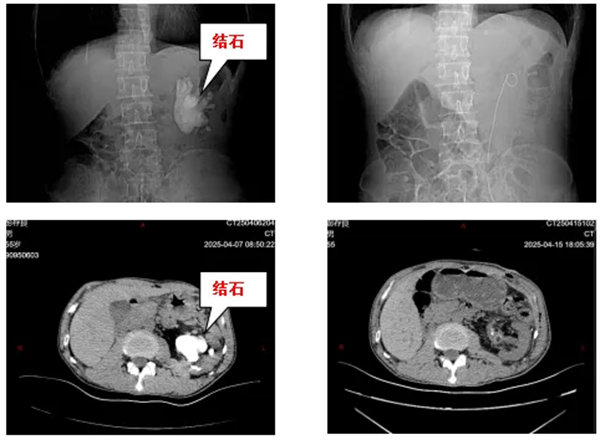

近日,宝鸡市人民医院泌尿外一科接诊了一位特殊患者。张先生(化名)因持续腰痛就医,检查结果令人震惊:该患者只有一个肾,且唯一的左肾内竟藏有一个直径达8cm的巨型铸型结石,形如“鹿角”般盘踞整个肾盂系统,且质地异常坚硬,与肾盂黏膜紧密粘连。对于独肾患者而言,这不仅关乎疼痛,更是一场生死考验!

经过3小时的精细操作,医疗团队成功完整取出所有结石分支。术后检查显示患者肾盂系统通畅,肾功能指标稳定。患者术后恢复顺利,术后一周即康复出院。